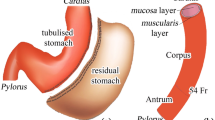

For each patient two models were reconstructed, i.e., the physiological (pre-surgical) stomach and the corresponding sleeved stomach at six months after surgery. The segmentation of the MRI scans led to the generation of 46 virtual solid stomach models (#23 pre-surgical stomachs + the corresponding #23 sleeved stomachs) by means of Synopsys Simpleware ScanIP. The specifics of the scanner machine and image resolution are reported in [22]. The volumetric identification was done from the MRI sequences of an empty stomach in the transverse plane, considering the optimal view for the recognition of gastroesophageal junction. The segmentation considered the whole stomach to the pyloric ring. The stomach volumes obtained were checked in the coronal plane and then exported. A double-layered geometry was generated from subsequent offsets of the external stomach surface, to obtain the submucosa-mucosa and muscularis layer (Fig. 1a) by means of Solidworks (Dassault Systemes, 2018). Different constant thicknesses were assigned to the submucosa-mucosa and muscularis layer, according to the considered gastric region, such as 0.9 and 1.2 mm in the fundus, 1.2 and 1.5 mm in the corpus, and 0.9 and 1.8 mm in the antrum, respectively [37, 39] (Fig. 1a).

The development of a patient-specific stomach model for finite element simulations. a From MRI the inner volume of the stomach is extracted; then the submucosa and the muscularis layer are created by means of surface offsets, with different thicknesses depending on the specific gastric region and layer. b Fine elements mesh of both the layers: six hexahedral elements modeled both the submucosa-mucosa layer and the muscularis stratum along the thickness direction